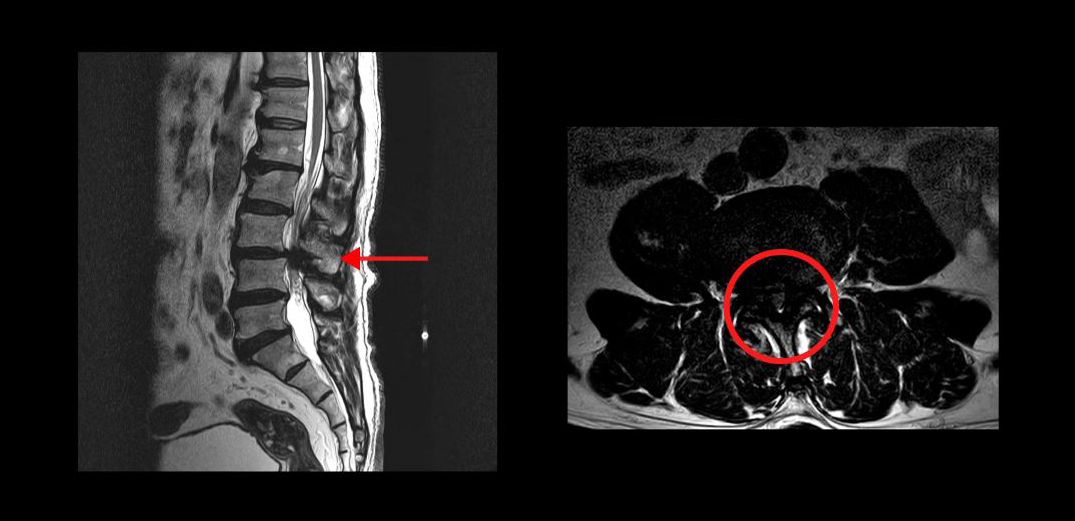

또 다른 한 분은 척추관이 심하게 막혀있는 중심성 척추관협착증 환자분입니다. MRI를 보시면 한 마디가 심하게 막혀있죠. 이분은 10년 이상 협착증 증상을 앓다가, 결국 걷기만 하면 다리에 힘이 빠져버려서 아무데라도 주저 앉아야 하는 극심한 신경성 파행 증상을 겪으셨습니다. 서울의 유명 대학병원에서 수술을 하기로 했지만, 결국 심장 문제 때문에 수술을 못 받으셨습니다.